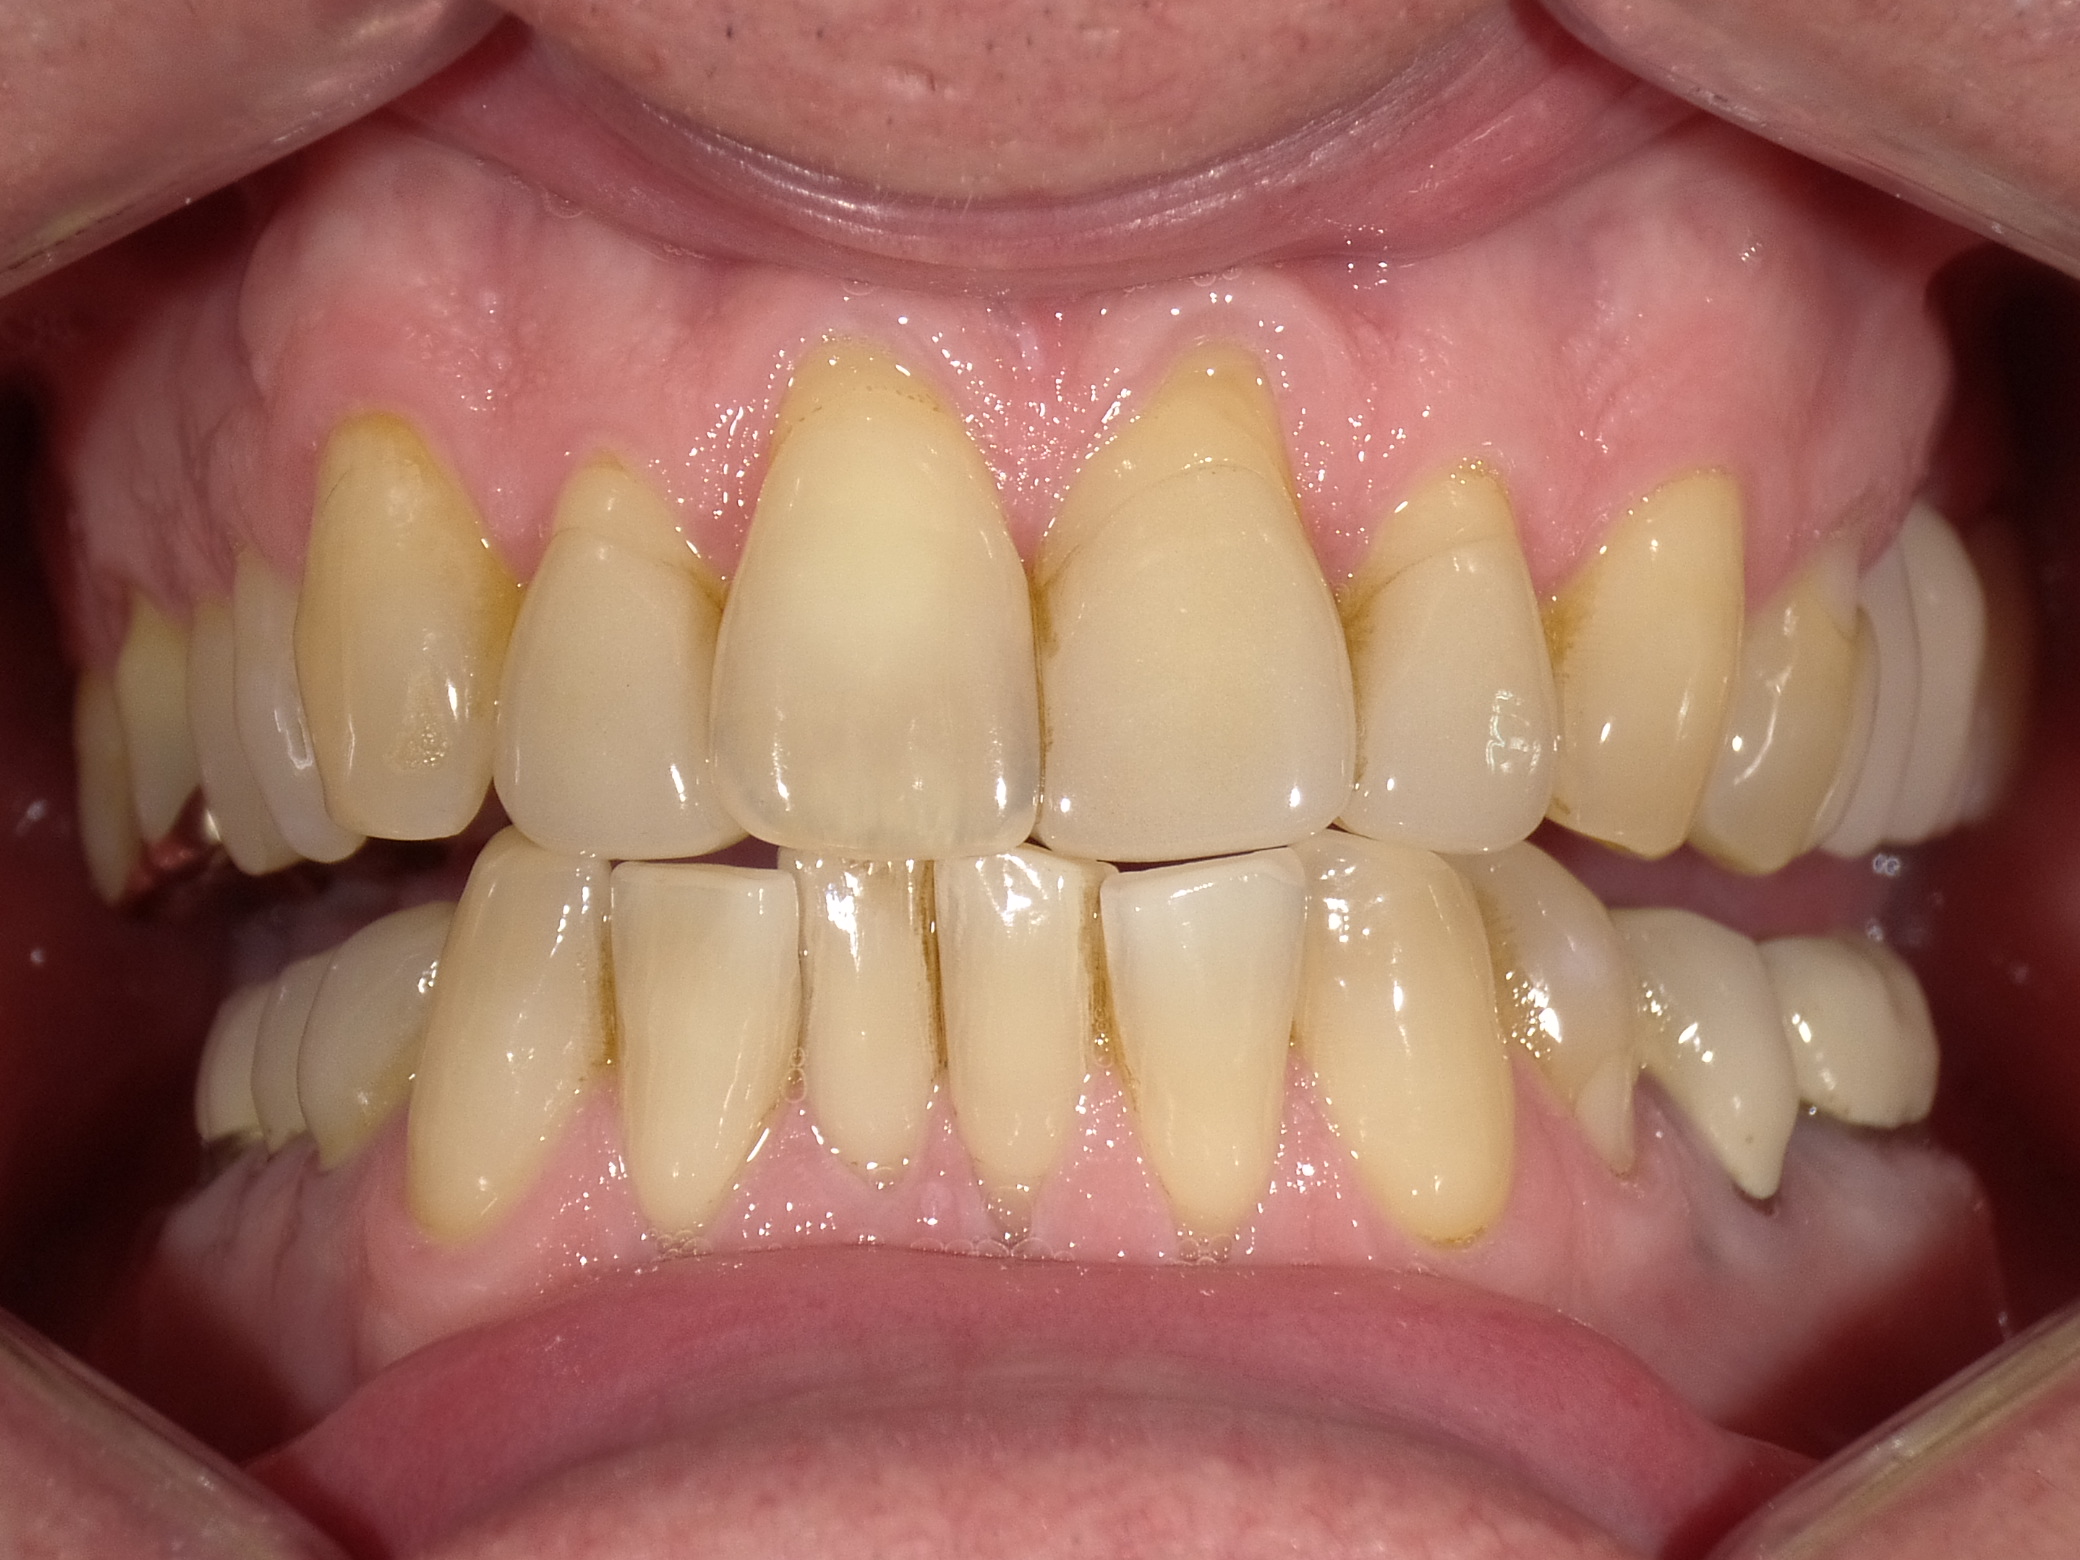

Abradierte, gelbliche Zähne mit vielen Kunststoff-Füllungen und Kronen, die der Patientin nicht gefallen haben

Vorher: Abradierte, gelbliche Zähne mit vielen Kunststoff-Füllungen und Kronen, die der Patientin nicht gefallen haben

Leuchtende Zähne durch vollkeramische Veneers und Teilkronen in nur 2 Terminen

Nachher: Leuchtende Zähne durch vollkeramische Veneers und Teilkronen in nur 2 Terminen